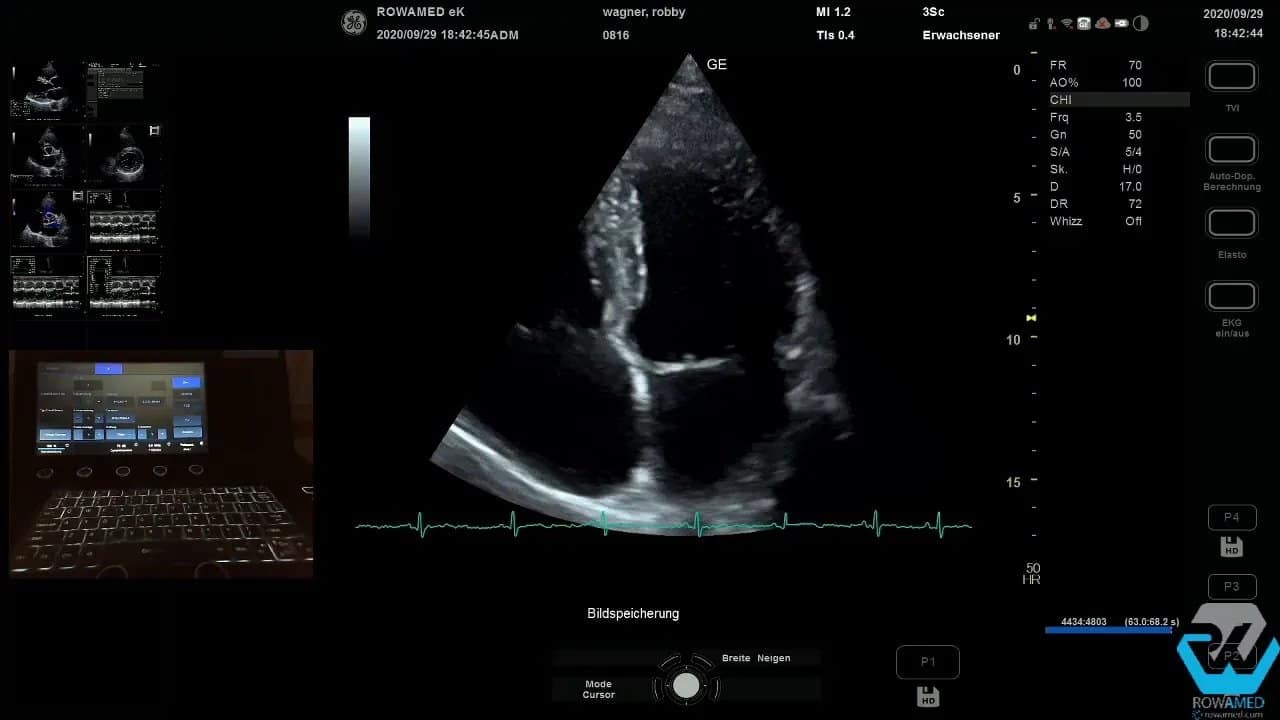

Step 7: Den apikalen Vierkammerblick optimieren

Nach Abschluss der parasternalen Ebenen folgt die apikale Anlotung. Häufig braucht es dafür nur eine kleine Lagerungskorrektur. Der Patient rutscht etwas nach vorne, der Schallkopf kommt besser unter den Thoraxrand, und plötzlich wird aus einem mittelmäßigen ein sehr guter Vierkammerblick.

Wenn das Bild grobkörnig wirkt, können Sie mit Bildglättung oder Frame Average arbeiten. Dadurch wirkt die Darstellung harmonischer, ohne dass relevante Strukturen verloren gehen. Solche Funktionen sind in modernen Systemen ausgesprochen nützlich, solange sie bewusst und nicht übermäßig eingesetzt werden.

Im apikalen Vierkammerblick beurteilen Sie zunächst wieder die linksventrikuläre Kinetik. Im vorliegenden Fall pumpte der linke Ventrikel hervorragend. Diese visuelle Einschätzung ist wichtig, sollte aber idealerweise durch eine quantitative EF-Bestimmung ergänzt werden.